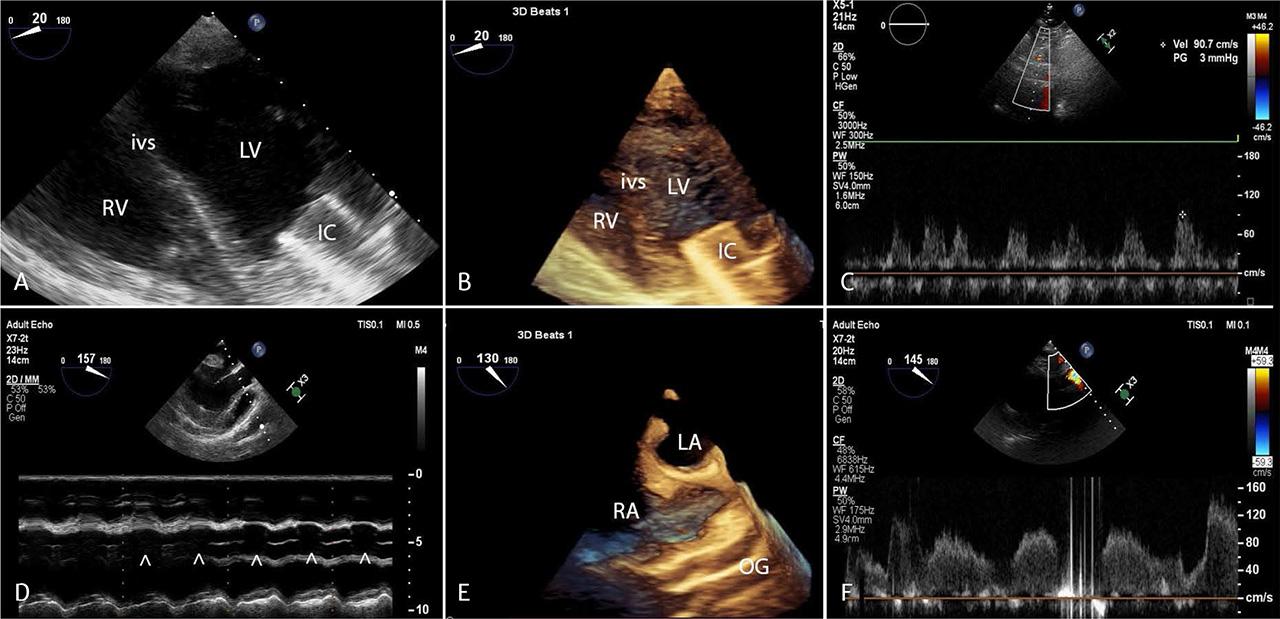

FIGURE 2.